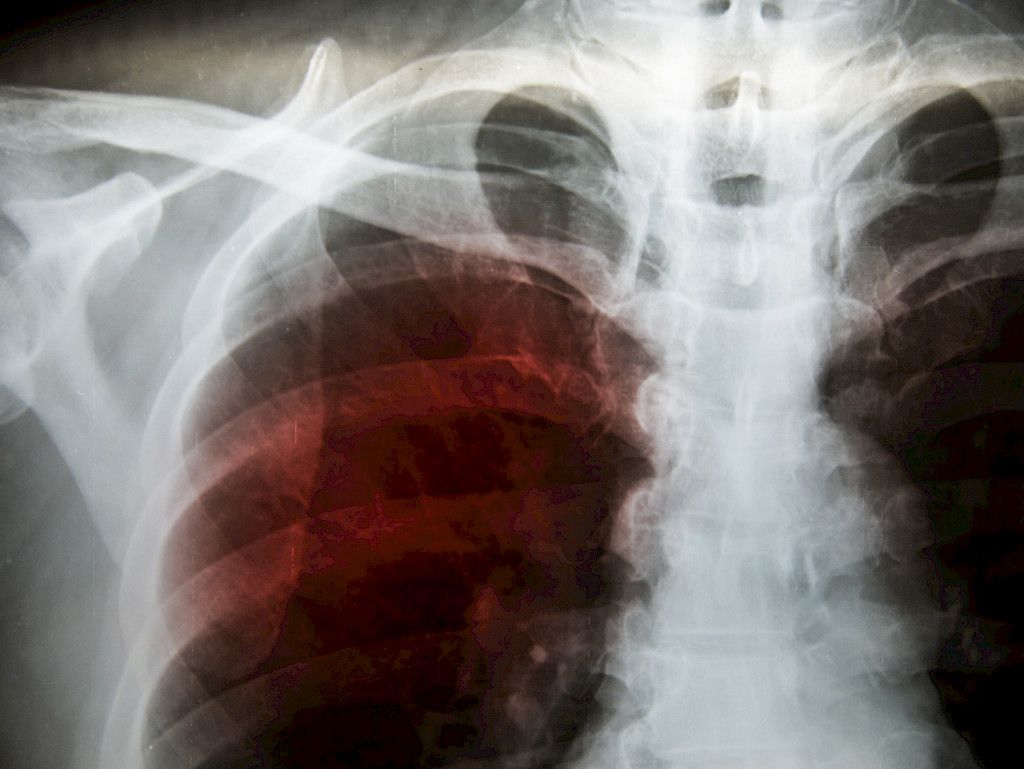

Keuhkoröntgenkuva on helppo, halpa ja nopea seulontatutkimus, jota kannattaa käyttää matalalla kynnyksellä.

Kun lääkäri kohtaa Ukrainasta tulleen pakolaisen vastaanotollaan, on hyvä pitää mielessä myös tuberkuloosin mahdollisuus. Etenkin infektio-oireiselta potilaalta kannattaa ottaa keuhkoröntgenkuva ja myös yskösnäytteet, jos tuberkuloosista herää pienikin epäilys.

– Ei ole väärin ottaa keuhkoröntgenkuvaa, vaikka potilas olisi päätynyt terveydenhuoltoon muustakin syystä. Se on helppo, halpa ja nopea seulontatutkimus, ja sen säderasitus on pieni, suosittelee professori, keuhkosairauksien erikoislääkäri Tuula Vasankari .

– Moni yskä ja infektio-oireilu menee nyt koronan piikkiin. Koronan, tuberkuloosin ja keuhkosyövän oireet voivat olla melkein samanlaisia. Näissä oireissa keuhkoröntgen on halpa ja elämän pelastava tutkimus, Vasankari muistuttaa.